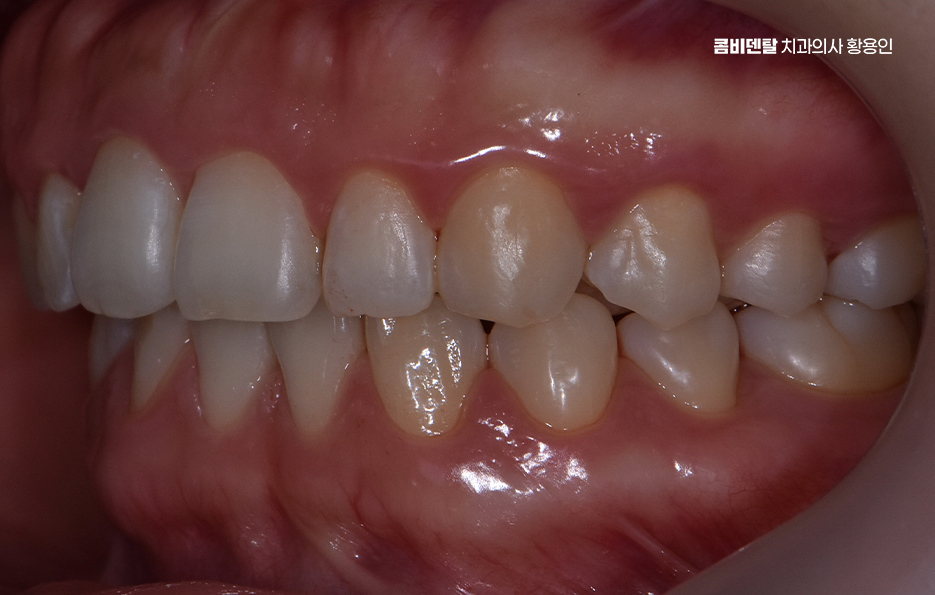

일반적으로 발치를 동반하는 교정의 경우, 통증이 좀더 더 심할 수 있는데 발치를 하면 인접한 치아가 그 빈 공간을 메우기 위해 이동하고 이 과정에서 기존보다 더 강한 힘이 가해지면서 불편함이 커질 수 있어요.

또한, 발치 후에는 잇몸이 아물어야 하고, 이후 치아가 이동하면서 추가적인 압력이 가해지기 때문에 교정 초반에는 상대적으로 더 많은 통증이 발생하게 된다는 점에서는 자신이 발치교정에 해당되는지 비발치교정으로도 가능한지 여부를 잘 구분해본다면 이러한 불편함을 감수해야 하는 정도를 파악하는데 도움이 되며 발치교정을 하더라도 시간이 지나면서 발치 후 통증을 가라앉기 때문에 통증이 심해지는 시기에 식사 조절이나 진통제 등의 적절한 조치를 통해서 치아교정 통증 줄이는 방법 또한 있어요